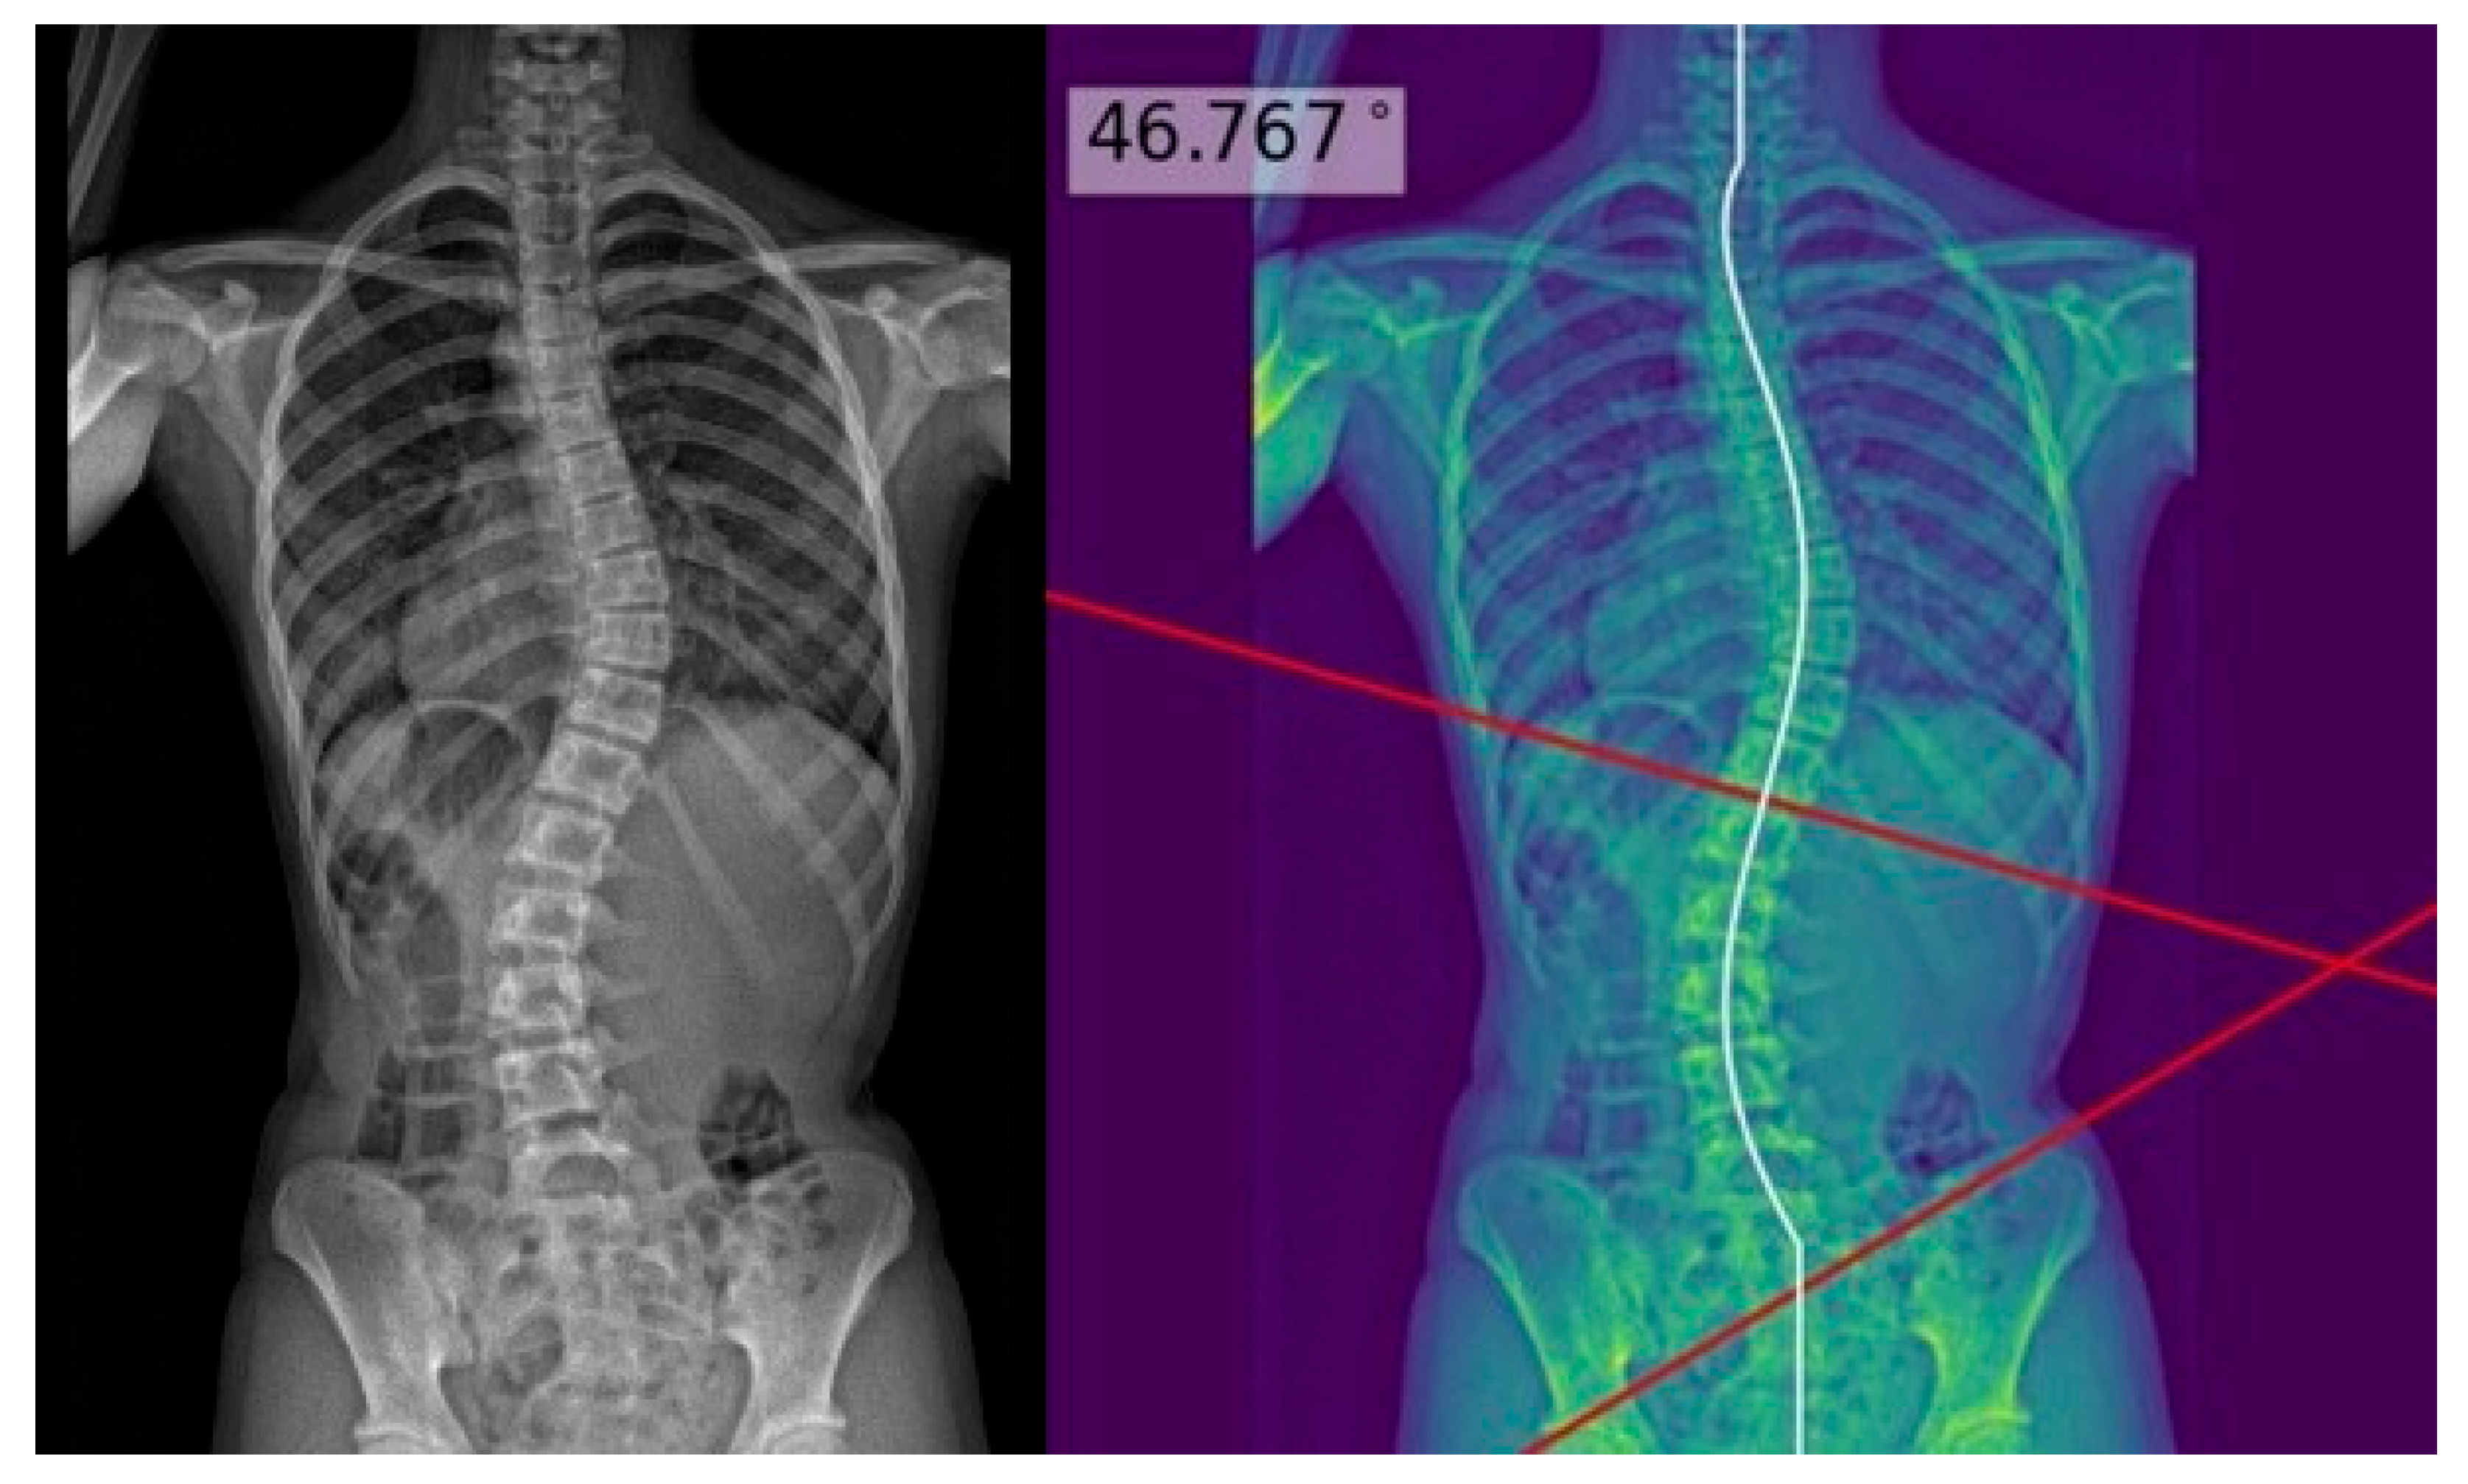

The process above allowed deep learning model masks of the whole spine (showing individual vertebrae) to be obtained and compared to the manual annotations. The model achieved a Dice similarity coefficient of 0.88 and Intersection over Union (IOU) of 84% on validation; it achieved a Dice coefficient of 0.619 and IOU of 72% on testing. Using the masks, the deep learning model determined the center of each vertebra, and extrapolated a polynomial curve along the centers. The spline technique, or the exhaustive assessment of the maximum angles between the vertebrae center line pairs to determine the largest angle, was the method of choice for the measurement of Cobb’s angle. Once the model has identified the correct points on the line, the reader could view the model prediction as extended lines and text in the top right hand corner of the image. For physicians’ review and augmentation, the model (available at the following web server: https://radweb.sha.endeavour-poc.ai/, accessed on 1 May 2022) annotated the largest possible angle in the output images, as shown in Figure 2 and Figure 3. Appendix A provides more details on the deep learning model.

The readers performed manual measurements of the major coronal curve angle without assistance from the deep learning model using the digital angle tool on the Picture Archiving and Communication System (PACS) (Centricity, GE Healthcare, Chicago, IL, USA), with the results overlaid on the images. When interpreting the radiographs with assistance from the deep learning model, the readers accessed the automated major coronal curve calculations and annotations overlaid on the images (as illustrated in Figure 2 and Figure 3). The readers could accept the model predictions or perform manual calculations using the same digital tool as per their clinical judgment, especially if the center curve alignment did not match the image.

Figure 3. Posteroanterior whole-spine radiograph for scoliosis assessment (left) with the deep learning model polynomial curve (fitted to the centers of the vertebrae) and Cobb’s angle prediction overlaid on the image (right). This is an example of a poor model prediction as it was not fitted to the inferior curve, with more than 10 degrees of difference from the reference standard Cobb’s angle.